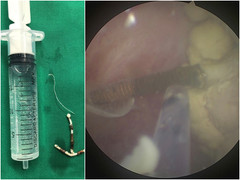

"Túi thừa bàng quang giống như quả bom có thể vỡ ra bất cứ lúc nào và gây nên nhiều biến chứng nguy hiểm. Do đó, với trường hợp này, các bác sĩ đã lựa chọn phương pháp phẫu thuật nội soi cắt túi thừa bàng quang và trả lại bàng quang khỏe mạnh cho người bệnh", bác sĩ Thịnh cho biết.